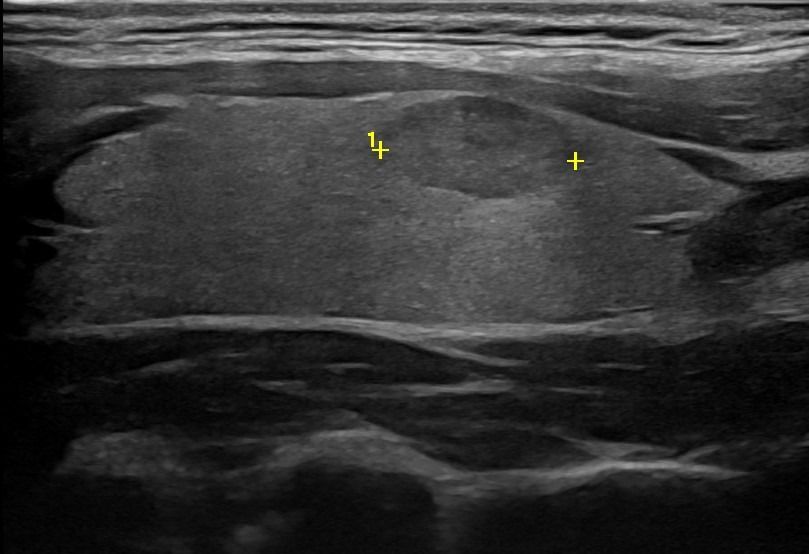

Με την τριπλή μελέτη του Θυρεοειδούς Αδένα, που περιλαμβάνει το B-Μode, το Έγχρωμο Υπερηχογράφημα και την Ελαστογραφία, γίνεται μια ολοκληρωμένη χαρτογράφηση του θυρεοειδούς αδένα. Το περίγραμμα, η αγγείωση και η ελαστικότητα του αδένα, καθώς και η υφή μίας πιθανής βλάβης αξιολογούνται με ακρίβεια και αξιοπιστία.

• Εστιακές αλλοιώσεις (όζοι του θυρεοειδούς αδένα)

Το Υπερηχογράφημα επιπλέον αποτελεί ιδανική μέθοδο για την απεικόνιση των παραθυρεοειδών αδένων και την ανίχνευση πιθανών αδενωμάτων ή άλλων βλαβών. Η υψηλή ευκρίνεια των εικόνων εξασφαλίζει την αξιόπιστη ανίχνευση και αξιολόγηση τους.